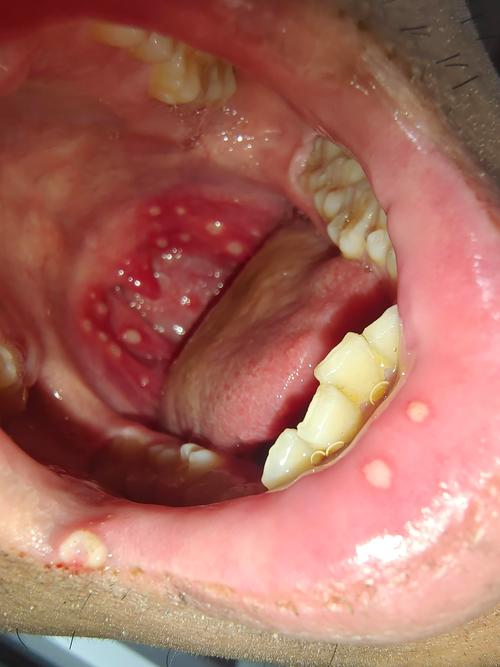

图片2:重型口腔溃疡(颊部内侧)

这张图片显示在口腔内侧颊部有一个非常大的溃疡,由于位置靠近牙齿,患者在张口或进食时会感到剧痛,可以看到溃疡边缘隆起,底部凹陷,是典型的“火山口”外观。

图片3:重型口腔溃疡(软腭)

这是一个发生在软腭的重型口腔溃疡,软腭部位的活动频繁,吞咽动作会直接刺激溃疡,导致疼痛感异常强烈,溃疡面积大,且周围组织充血明显。